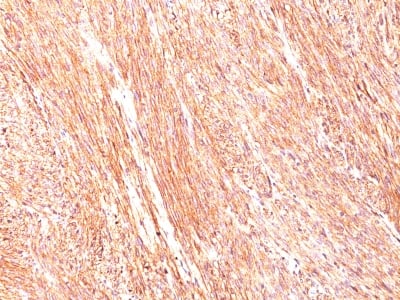

Expression of DOG-1 protein is elevated in the gastrointestinal stromal tumors (GISTs), c-kit signaling-driven mesenchymal tumors of the GI tract. DOG-1 is rarely expressed in other soft tissue tumors, which, due to appearance, may be difficult. Immunoreactivity for DOG-1 has been reported in 97.8 percent of scorable GISTs, including all c-kit negative GISTs. Overexpression of DOG-1 has been suggested to aid in the identification of GISTs, including Platelet-Derived Growth Factor Receptor Alpha (PDGFR alpha) mutants that fail to express c-kit antigen. The overall sensitivity of DOG1 and c-kit in GISTs is nearly identical: 94.4% vs. 94.7%.

Gastrointestinal Stromal Tumor (GIST) or testicular germ cell tumor. Melanocytes in the basal layer of the epidermis and mast cells in the dermis of normal skin.